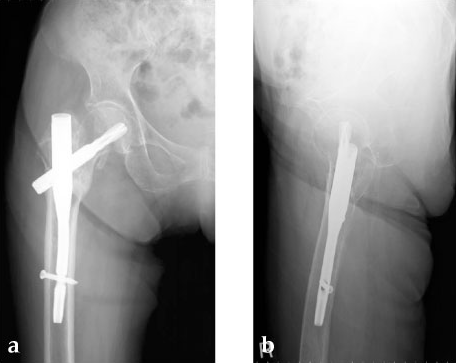

She was operated on the next day and fixed with a PFNA Asia (size: extra small, angle 130 degrees, distal diameter: 9 mm, blade length 100 mm) (Fig 6a). Good reduction and stable fixation were obtained. Full weight-bearing gait was allowed on the second postoperative day. There was an uneventful postoperative course, and good union was obtained at three months after surgery (Fig 6b).